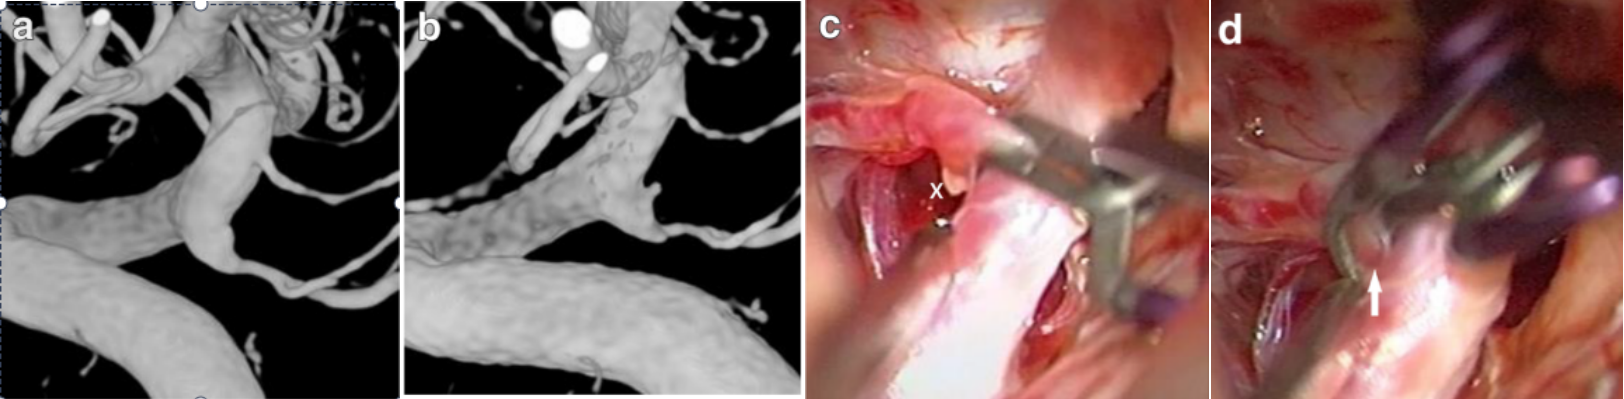

图1. 27岁男性突发头痛。a.造影提示左侧后交通膨大,余未见明显异常。b.5天后复查造影提示后交通膨大突出小泡较前明显。c.开颅术中可见后交通膨大旁血凝块(图中标示x),进一步确认责任病变。d.两把平行颈动脉动脉瘤夹,夹闭膨大段,后交通血供来源于后循环。